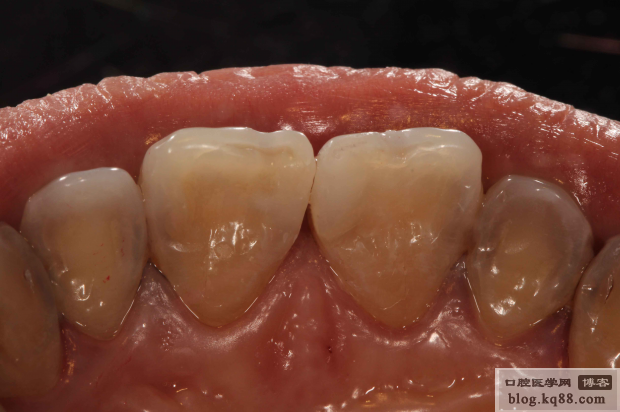

隔日高光澤度拋光